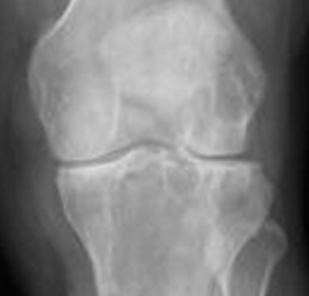

Fig 191. Artritis reumatoidea.

Rx AP. Disminución simétrica de los espacios femorotibiales, en ausencia de osteofitos, por artritis reumatoidea incipiente.